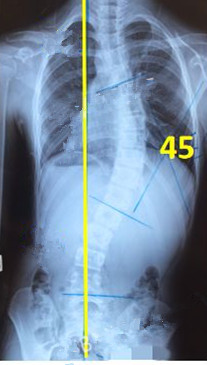

脊柱側(cè)彎患者的支具矯正

脊柱側(cè)彎矯形器(支具)是通過(guò)外力對(duì)側(cè)彎的脊柱進(jìn)行矯正。所以,支具的力點(diǎn)位置及大小非常重要。當(dāng)患者生長(zhǎng)發(fā)育速度較快或支具矯正效果較好時(shí),側(cè)彎矯正的進(jìn)程也會(huì)較快,此時(shí)為了充分利用孩子生長(zhǎng)階段的最佳矯正期,一定要對(duì)支具進(jìn)行及時(shí)的調(diào)整和更換。

一般經(jīng)過(guò)三個(gè)月至六個(gè)月的治療,對(duì)稱度都能得到改善,力線回正。

此時(shí)由于患者已經(jīng)完全適應(yīng)支具的力點(diǎn),且體表變化較大,為了進(jìn)一步矯正,我們需要對(duì)支具進(jìn)行調(diào)整。如果由于孩子身高的變化較大,為了更進(jìn)一步的矯正,可以考慮更換新的支具。

未穿支具

穿支具后